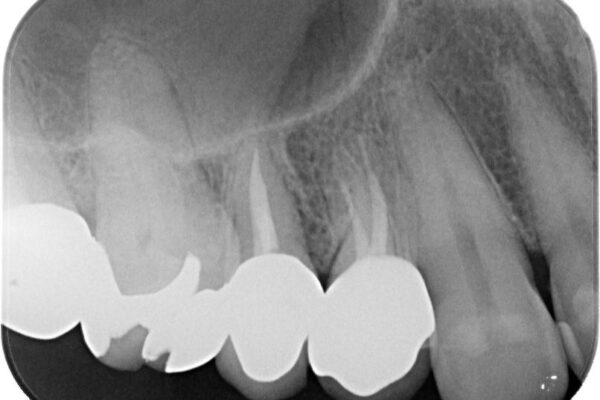

「以前治療した歯の被せものが外れてしまった」とのことで、右上の小臼歯の被せもの脱離を主訴に来院されました。

診察の結果、被せもの(クラウン)だけでなく、土台(コア)ごと外れてしまっている状態でした。根管治療済みの歯ではありますが、今回患者様のご希望により、根管治療の再治療は行わず、補綴処置のみを行う方針となりました。

残存歯質の確認と感染リスクのチェック

治療前

• 自然な美しさと強度を両立!右上小臼歯の被せもの脱離に対する審美補綴治療 治療前画像